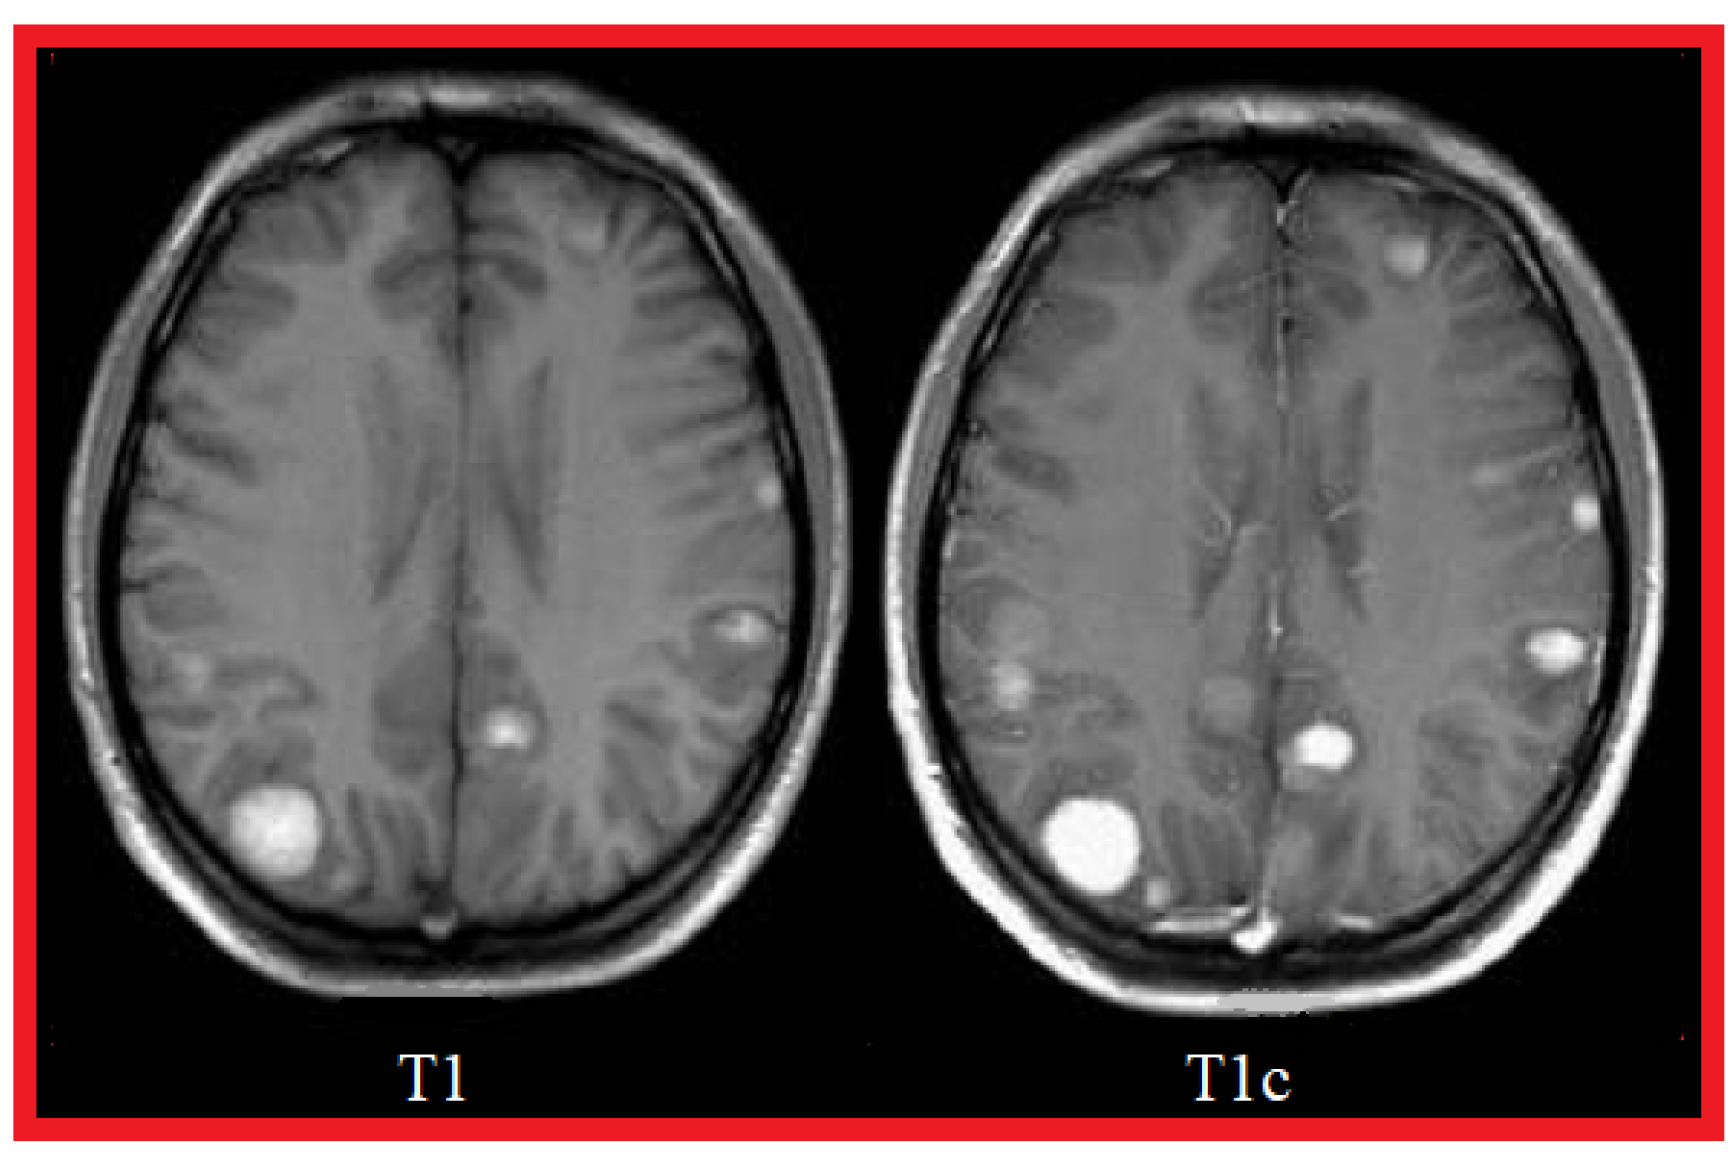

1.2. MRI Sequences for Brain Tumors